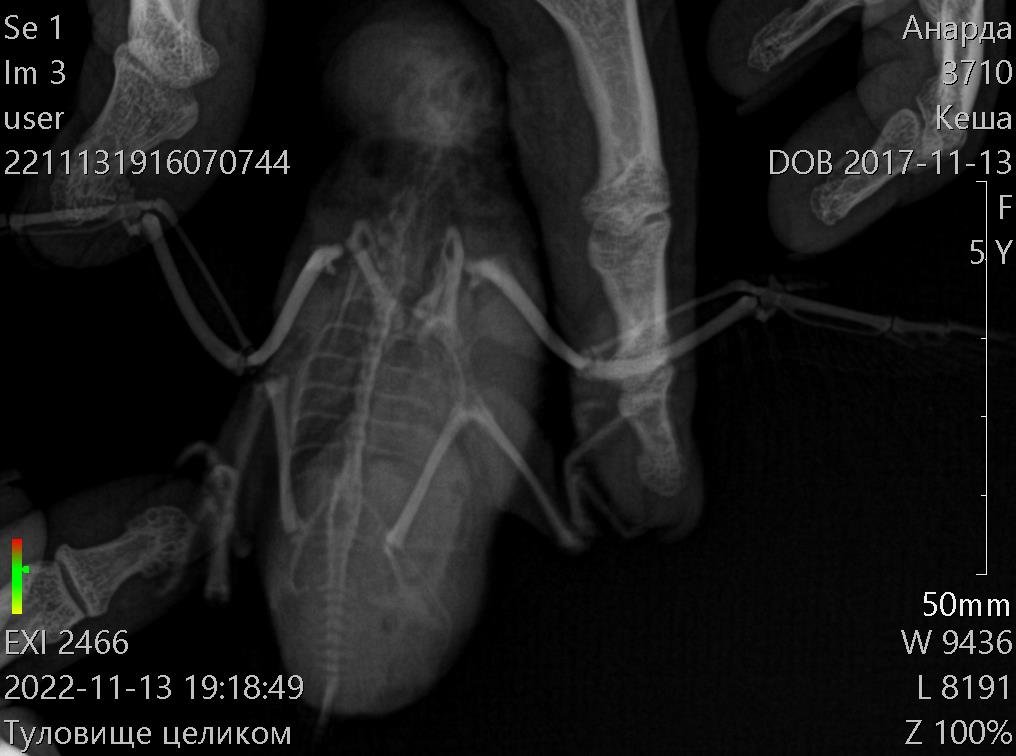

Здравствуйте! Пожалуйста, помогите моему волнистику. Больше месяца назад начались проблемы с калом. Начал какать редко и большими кучками. Сначала не придала значения, а потом у него начался сильнейший запор. Кеша перестал есть, пить, не мог вообще сходить в туалет. Орнитологов у нас нет в городе. После изучения информации на форумах, пропоила его биссептолом суспензией, кормили кашей и поили со шприца. В клюв капала вазелиновое масло. В еду линекс сыпала. Сейчас измельчаю карсил и добавляю в сухой корм. Ему стало легче, кал так и восстановился. Ходит большими кучками. Стал тяжело дышать, плохо и мало летать. На животе появилась опухоль. Сдали анализы на криптоспоридиоз и сальмонеллез- отрицательные. Сделали ренген. По результатам- проблемы с легкими и опухоль. Что делать? Умоляю, помогите!